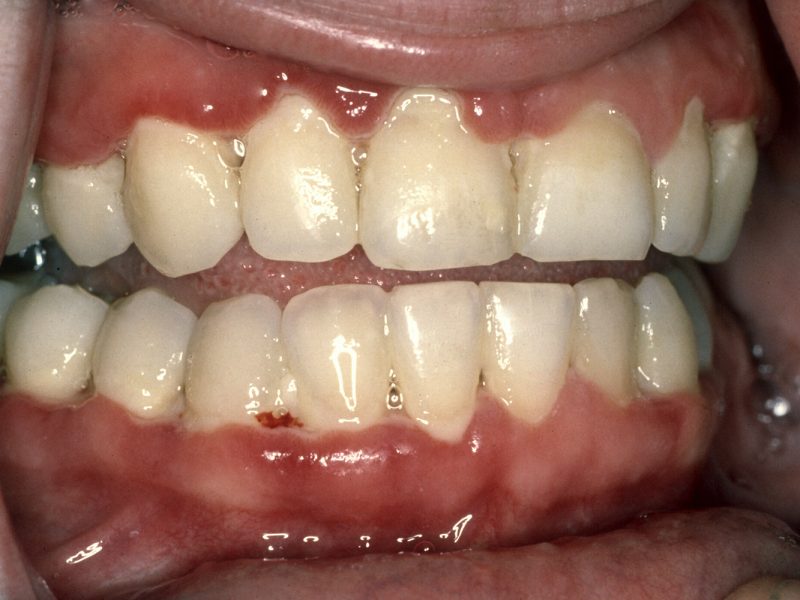

La gingivitis es conocida como la inflamación de las encías, y la presencia de dolor en las encías porque se hinchan y se enrojecen, y…